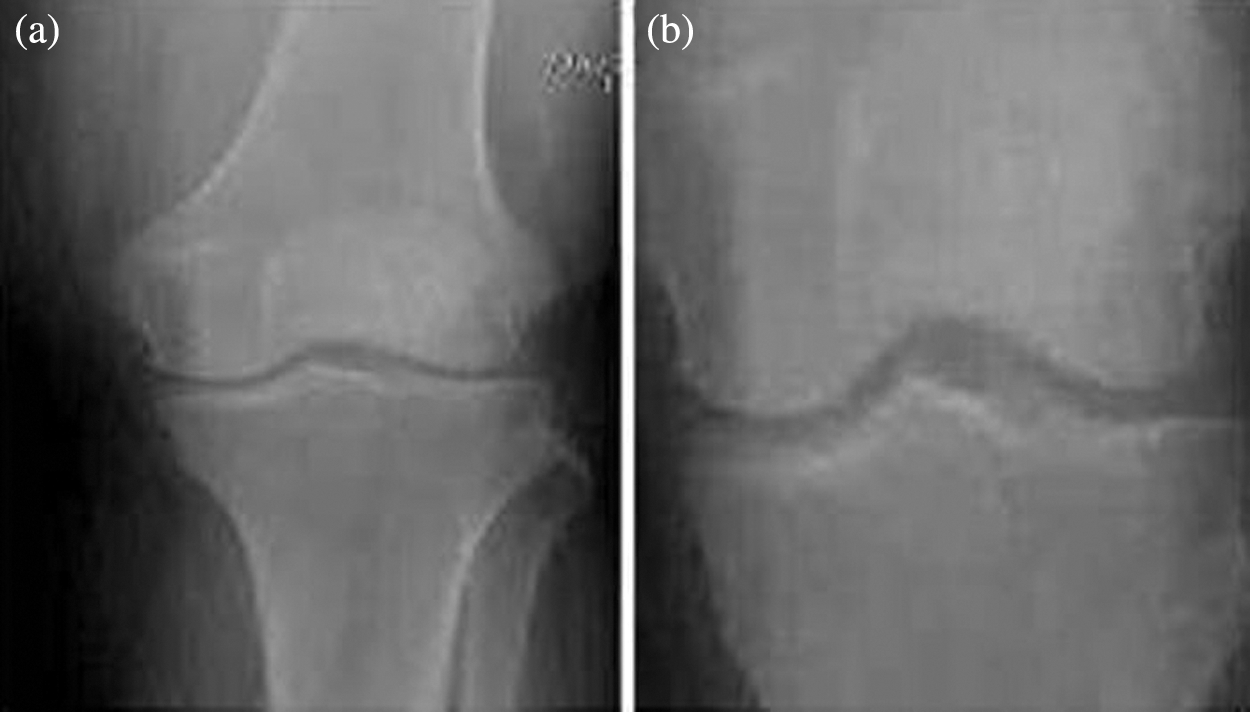

From the experimental analysis, it is obvious that the osteoarthritis can be analysed and processed by this technique. As we mentioned in Fig. 6b the input CT image is enhanced using correlation histogram analysis that increased the intensity of the image. In Fig. 6c thresholding concept is applied that segmented the enhanced CT image based on Niblack and Bernsen algorithm as shown in Fig. 6d. Finally the segmented image is optimized using Elephant Herding optimization that isolated the osteoarthritis. Experimental result of the proposed technique is compared with different existing techniques to evaluate its performance.

Figure 6: Experimental result of the proposed method with CT image samples (a) Sample images (b) Contrast enhanced image using correlation histogram (c) Thresholding (d) Niblack and Bernsen output (e) EH Optimized image